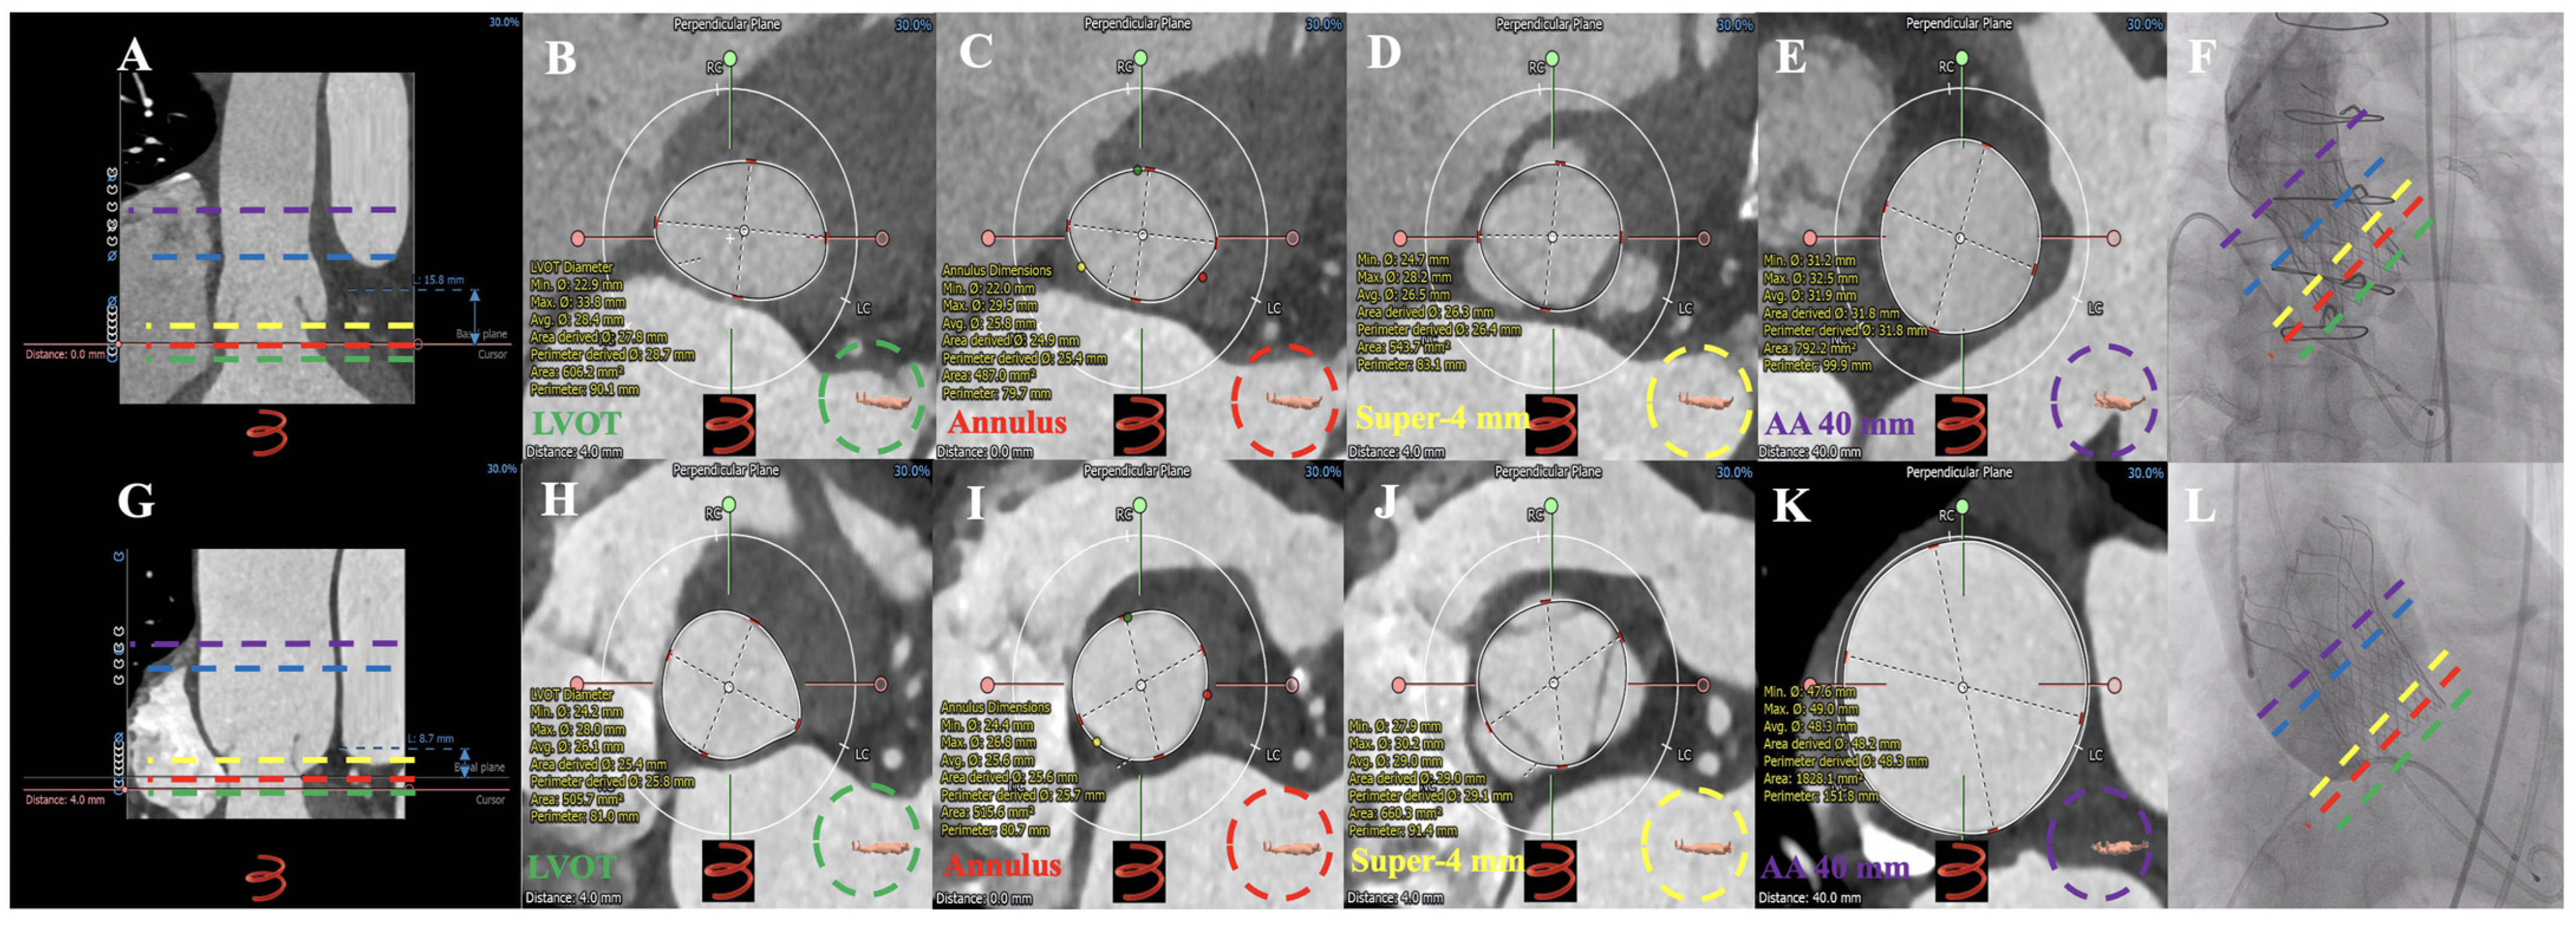

3.2. MDCT Evaluation and Anatomical Classification

| Dual-anchoring multiplane measurement (diameter calculated by the perimeter, mm) | ||||||

| Sup-2 mm | 26.2 ± 2.6 | 25.7 ± 1.7 | 27.5 ± 1.7 | 25.5 ± 2.3 | 29.3 ± 5.0 ac | 0.040 |

| Sup-2 mm | 26.7 ± 2.0 | 26.4 ± 1.6 | 27.9 ± 1.4 | 26.7 ± 2.3 | 26.8 ± 2.9 | 0.715 |

| Sup-4 mm | 28.3 ± 2.1 | 28.2 ± 1.8 | 29.4 ± 2.0 | 28.4 ± 2.5 | 27.0 ± 2.4 | 0.516 |

| Sup-6 mm | 29.6 ± 2.2 | 29.4 ± 2.0 | 31.1 ± 2.0 | 29.8 ± 2.2 | 28.0 ± 2.8 | 0.295 |

| Sup-8 mm | 30.5 ± 2.4 | 30.1 ± 1.7 | 31.8 ± 4.5 | 31.1 ± 2.5 | 28.8 ± 2.9 | 0.254 |

| Sup-10 mm | 31.2 ± 2.6 | 30.6 ± 1.8 | 32.4 ± 5.0 | 32.2 ± 2.6 | 30.0 ± 3.0 | 0.212 |

| Sup-min | 26.6 ± 2.0 | 26.4 ± 1.7 | 27.9 ± 1.4 | 26.7 ± 2.3 | 26.2 ± 2.9 | 0.686 |

| AA-30 mm | 37.7 ± 5.4 | 34.2 ± 2.8 | 36.1 ± 5.8 | 42.5 ± 5.2 ab | 38.5 ± 2.6 | 0.000 |

| AA-35 mm | 38.7 ± 5.4 | 35.3 ± 2.9 | 35.3 ± 4.0 | 43.6 ± 5.4 ab | 39.0 ± 2.7 c | 0.000 |

| AA-40 mm | 39.7 ± 5.4 | 36.6 ± 3.1 | 36.2 ± 3.8 | 44.6 ± 5.3 ab | 39.5 ± 3.4 | 0.000 |

| AA-45 mm | 40.6 ± 5.6 | 37.5 ± 3.6 | 36.9 ± 3.9 | 45.5 ± 5.4 ab | 40.7 ± 3.2 | 0.000 |

| AA-50 mm | 41.6 ± 6.1 | 38.0 ± 4.1 | 37.7 ± 3.8 | 46.3 ± 5.4 ab | 44.6 ± 5.9 a | 0.000 |

| AA-min | 37.5 ± 5.2 | 34.2 ± 2.8 | 34.9 ± 4.7 | 42.2 ± 4.8 ab | 37.9 ± 2.3 | 0.000 |